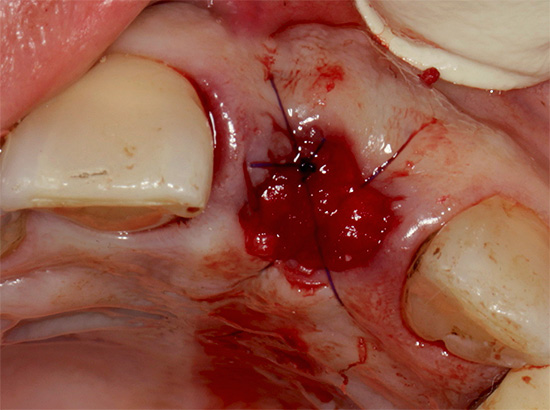

Se a cicatrização do tecido ocorrer sem problemas, um poço normal deve parecer algo como 1-2 em 1-2 dias:

Apesar da cor característica, você não deve confundir um coágulo sanguíneo normal com pus e temer que uma mudança de cor de Borgonha para mais clara já seja um sinal de alveolite. Além disso, você não precisa subir na ferida, pois isso pode danificar seriamente a cicatrização normal do buraco.

O processo de cicatrização normal (crescimento excessivo) do orifício após a extração do dente deve ser indolor.A ferida cura pelo princípio da tensão secundária, em outras palavras - há uma aproximação gradual de suas bordas. O principal fator de cicatrização é a proliferação do tecido de granulação, que logo é substituído pelo tecido ósseo jovem.